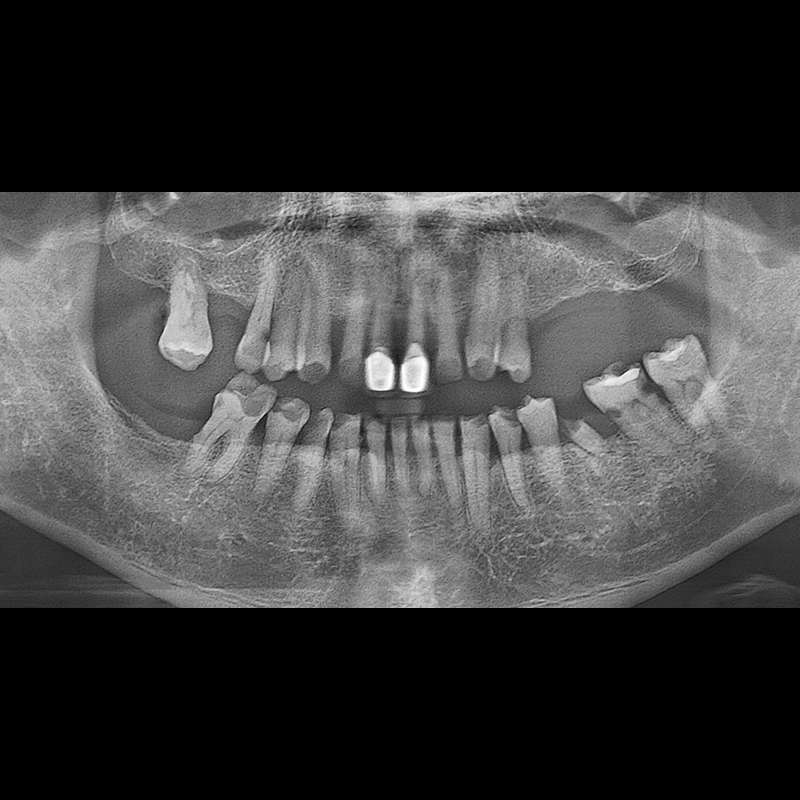

BEFORE AFTER

インプラント手術事例 2025.05.30

欠損した歯の部分と、生かしにくい歯の位置にインプラントを植立しました。